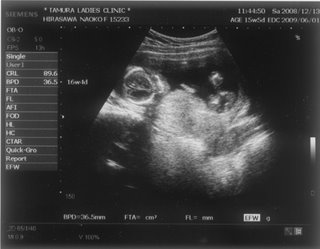

お腹の赤ちゃんは、今日で24週と4日。あっという間に7ヶ月突入です

![]() お腹もドンドン、食欲もドンドン出ていてあしたの4回目の検診コワーイ ![]() 妊娠発覚から三ヶ月半、なのにもう妊娠7ヶ月!頭がついていきません ![]() でも、毎日激しくなる胎動に感激している日々です ![]() 一回目の検診から4週後、2度目の検診に行ってきました。 2008年12月13日 赤ちゃんは15週と5日 ![]() 順調でした ![]() 左側から頭、胴体、足が写っていまーす ![]() 今回は4Dの機械も入り毎回撮影してくれるそうでーす ![]() 赤ちゃんは、ゴツゴツした背中だけを 見せ、顔はみせてくれませんでした~ ![]() それから4週後、3回目の検診。 2009年1月10日 赤ちゃんは19週と5日 ![]() 336gくらいになったようです ![]() 4D ようやく顔をみせてくれました ![]() かなりエイリアン ですが、フニュフニュ可愛かったです![]() 性別が わかりそうだったんですが、ソラ同様肝心なトコロをみせてくれませんでした ![]() もちろんどっちでもいいんですが、しりたーい ![]() 明日わかるかな ![]() ソラも赤ちゃんがテレビに映ったり、雑誌に載っていたり、 出かけ先で見かけたりすると、「ベイビー ![]() 」と大きな声で、何度も何度も興奮気味に言います ![]() 自分もまだまだ赤ちゃんなのに、「ベイビー」は自分より 小さくて可愛いものだと感じ始めているようです ![]() わたしは、一週間に1度だけ1歳になったばかりの 女の子を預かっています。 ソラは、その子が自分のオモチャを使うことに対して 少しイヤな気がしているようです ![]() 少し前までは「ドーゾー」と相手に有無を言わせず 何でも渡していたけど、どんどん自我が出てきているみたいですね~ そんな感じでオモチャを取り合いしながら、シェアすることも学んでいます。 でも女の子が寝ると、さすがに可愛いと思ったらしく、 頭をナデナデ、チュしていました ![]() こんにちわ☆